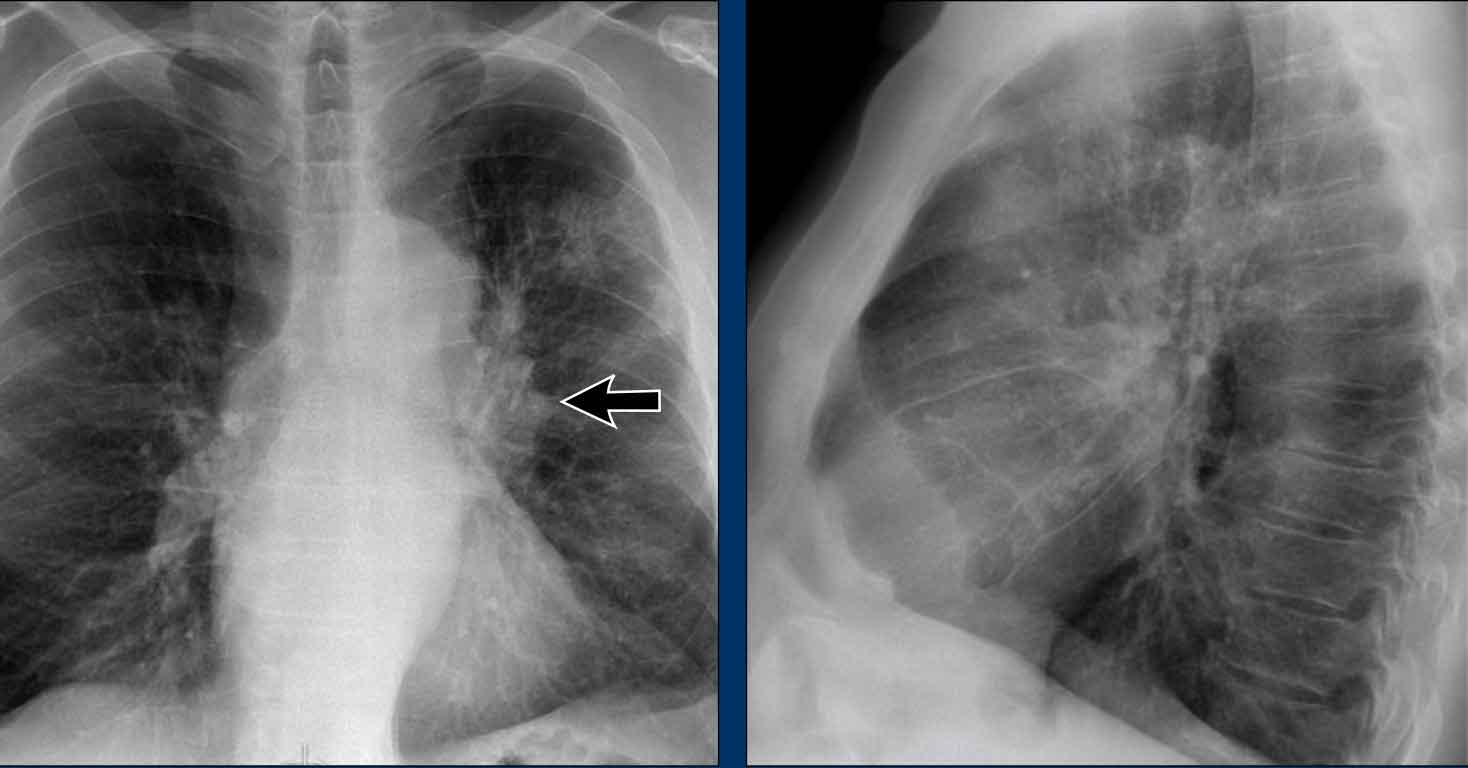

Hidden Areas (4): Retrocardiac Opacity

Initial review of the CXR reveals a subtle increase in density in the retrocardiac region (blue area), which requires careful attention.

• This was confirmed to be a left lower lobe pneumonia.

• Always correlate with the lateral view, where consolidation in the lower thoracic spine region is a key clue.